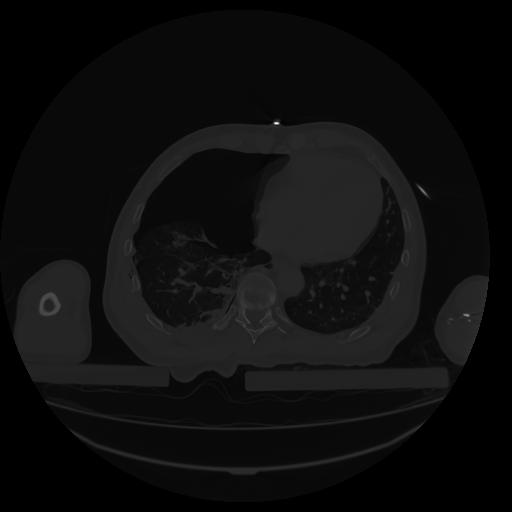

34 CUERPO,CE,Vol,1.0,CUERPO,,